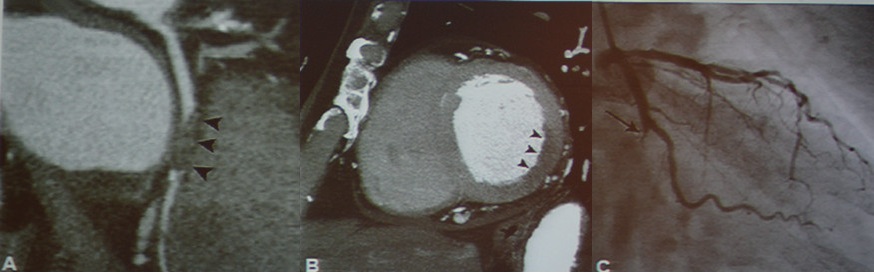

急性冠脉综合征:TRO可清晰地显示斑块、狭窄、闭塞和心肌缺血等病变。

图2-3 急性冠脉综合征